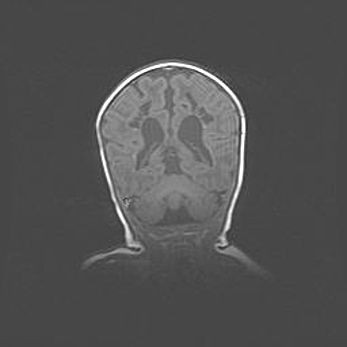

Неполная лизэнцефалия (пахигирия). Открытая гидроцефалия.

Возраст: 17 дней

Вес: 3110 г

Пол: мужской

Окружность головы: 33,5 см

Срок гестации: 35-36 недель

Лизэнцефалия—недоразвитие корковой пластинки и мозговых извилин в результате нарушения миграции нейронов коры. Поверхность мозговых полушарий гладкая. Микроскопически выявляется отсутствие нормальных слоев коры и скопление групп нейронов в подкорковом белом веществе.

Пахигирия—уменьшение числа вторичных извилин. В пораженном полушарии нервные клетки образуют толстый недифференцированный слой с неправильно расположенными нервными волокнами и группами гетеротопных клеток. Нервные клетки незрелые. Белое вещество истончено. При этом нередко аномально развит корково-спинномозговой путь.